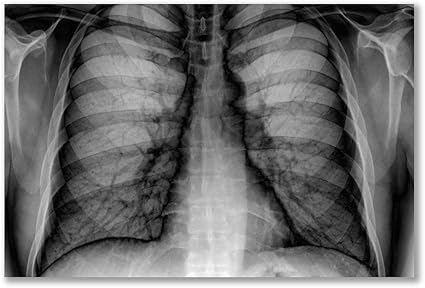

Radiografia del torace. è possibile visualizzare la presenza di cardiomegalia (rapporto diametro cuoretorace 05) e la presenza di edema polmonare ~ Viene effettuata per verificare le condizioni di cuore e polmoni Prova da sforzo. Le radiografie del torace possono perdere piccoli tumori polmonari potenzialmente curabili Se hai sintomi inspiegabili o fattori di rischio per il cancro del polmone, assicurati di parlare con il medico 0 cancro polmone cancro polmoni fattori rischio radiografia torace radiografie torace tumori polmonari. In radiologia, una radiografia del torace è una proiezione radiografica utilizzata per diagnosticare alcune patologie che colpiscono il torace, il suo contenuto e le strutture vicine Le radiografie al torace sono le radiografie più frequenti utilizzate in medicina.

In radiologia, una radiografia del torace è una proiezione radiografica utilizzata per diagnosticare alcune patologie che colpiscono il torace, il suo contenuto e le strutture vicine Le radiografie al torace sono le radiografie più frequenti utilizzate in medicina. Dal lato colpito il torace appare vuoto, venendo a mancare la presenza radiografica della normale struttura polmonare Nel caso del sospetto di bolle sottopleuriche, una TAC del torace consentirà di confermarne la presenza e di definirne la sede anche in previsione di un’eventuale soluzione chirurgica Come si cura lo pneumotorace?. La radiografia del torace è utile, per una prima valutazione, in caso di patologie autoimmuni del polmone, versamenti pleurici, lesioni polmonari di natura neoplastica, patologie infettive del polmone, (polmoniti, bronchite, broncopolmoniti, pleuriti, Tbc), bronchiti resistenti a terapie farmacologiche, ascessi, interstiziopatie ma anche tumori (es tumore al seno).

Le radiografie del torace possono anche fornire informazioni sulle condizioni dei polmoni;. Sottoponendosi ad una radiografia del torace il paziente non si sottopone ad alcun rischio immediato, questa indagine diagnostica è considerata sicuraL’esame prevede però l’utilizzo di radiazioni X, è fondamentale quindi che al paziente non vengano proposte radiografie inutili, per evitare l’esposizione ad un’eccessiva dose di radiazioni. L’RX del torace, o radiografia toracica, è un esame diagnostico che consente di ottenere immagini radiografiche delle ossa del torace, dei polmoni, del cuore e dei grandi vasi sanguigni vicino al cuore Questo esame consente anche di individuare la presenza di fluidi dentro o intorno ai polmoni o di aria nella pleura (la membrana formata da due “foglietti” rispettivamente a contatto con.

L’esame radiologico é un’indagine diagnostica che prevede l’utilizzo di particolari onde elettromagnetiche, i raggi X, in grado di attraversare il corpo umano e di essere misurati da un sistema fotosensibile (analogamente ad un sistema fotografico). L’esame radiografico del torace, anche chiamato “radiografia del torace” o semplicemente “RX torace”, è un esame diagnostico radiologico eseguito mediante l’uso di raggi X Il risultato dell’indagine è la tipica immagine in bianco e nero che evidenzia in modo differente le ossa e i parenchimi polmonari rispetto ai tessuti molli (muscoli e pelle), dal momento che le ossa sono. Ma la radiografia del torace svela la realtà la malattia si è fatta strada nei polmoni ed è visibile bianco su nero nelle 'lastre' Per la precisione, in 100 su 170 eseguite in una sola.

«La radiografia del torace può essere prescritta in tutti i casi in cui vi sia un sospetto diagnostico di patologia polmonare, come ad esempio una polmonite o un tumore – risponde il professor. Una radiografia del torace da sola non può confermare una diagnosi di BPCO, ma può fornire informazioni utili sui polmoni e sul cuore È inoltre necessario uno studio della funzionalità polmonare per fare una diagnosi affidabile, insieme a un'attenta valutazione dei sintomi e dell'impatto che i sintomi hanno sulla tua vita. L’esame radiografico del torace ( RX Torace) è un esame radiologico condotto mediante l’utilizzo di raggi X Il risultato è un’immagine che evidenzia in modo differente le ossa e i parenchimi polmonari rispetto ai tessuti molli (muscoli e pelle), perché le ossa sono strutture più compatte e appaiono più chiare rispetto agli altri tessuti.